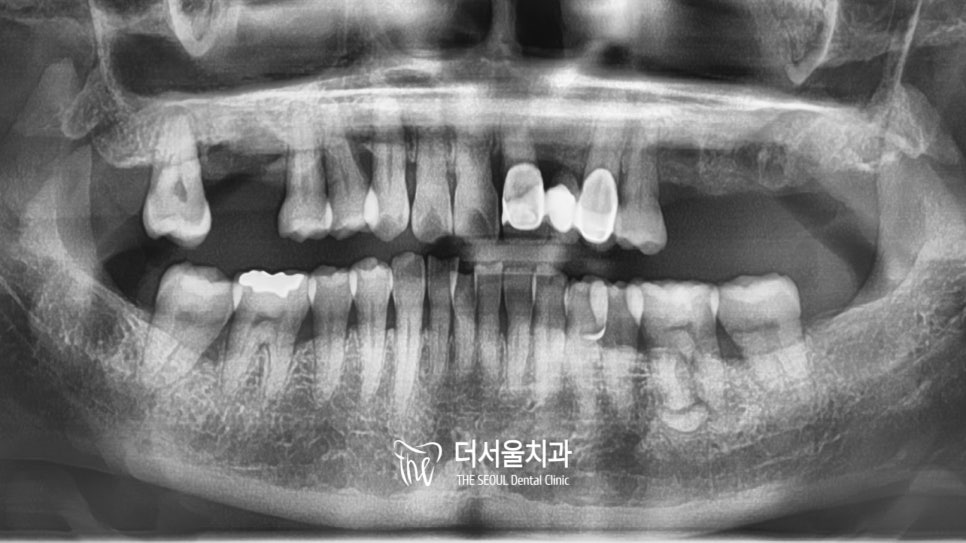

컴퓨터 분석을 통해

눈에 잘 띄지 않는 곳까지

확실하게 검진을 진행했습니다.

픽스쳐의 크기와 식립 방향, 각도

세밀한 부분을 파악하여

최선의 결과로 이어질 수 있게끔

하나라도 놓치지 않도록 진행했습니다^^

식립을 계획했던 곳을 발치했습니다.

잔존조직이 남아있지 않도록

몇차례 확인을 거쳐 진행했는데요.

발치를 하고 살펴보니

골소실이 일어난 곳이

더욱 눈에 띄게 나타나고 있습니다.